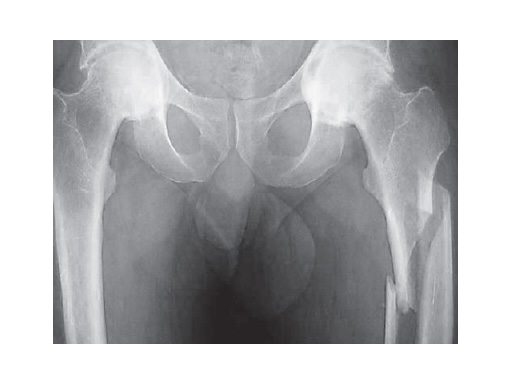

The LFN nail, with its two proximal locking options, (ie, retrograde (recon) and standard), is specifically indicated for the treatment of combined ipsilateral neck/shaft, subtrochanteric, and femoral shaft fractures with AO Classification 32-A, B, C and 31-B. With the recon locking option, two 6.5 mm screws can be inserted through the nail into the femoral neck and head. Alternatively, the LFN offers a standard proximal locking option with two 5.0 mm or 6.0 mm screws. Distal interlocking can be made by two static mediolateral, as well as one static oblique screw.